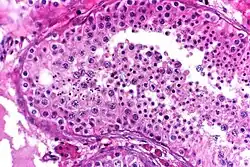

High-power view of a seminiferous tubule with normal spermatogenesis.